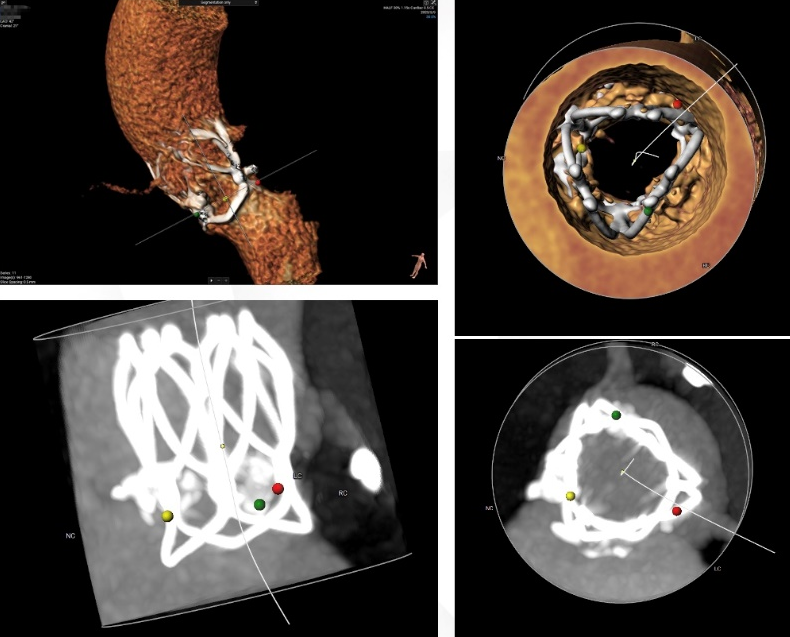

术前CT